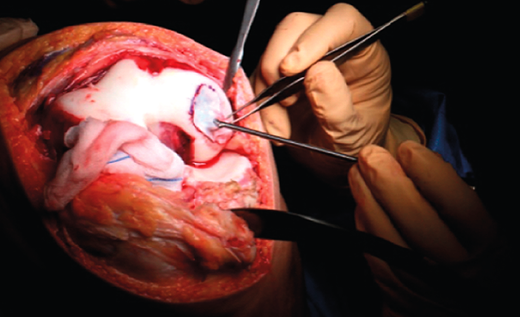

First surgery involves arthroscopy of the damaged joint. It assesses the chondral lesion to be treated and confirms whether it is amenable to the chondrocyte implantation technique (Figures 1 and 2). Other procedures are also carried out if needed, such as for example reconstruction of the anterior cruciate ligament, partial meniscectomies, meniscus implantation, patellar realignments, osteotomies, etc. Lastly, the cartilage sample is taken from a non-weight bearing zone (intercondylar zone or internal femoral condyle at its upper margin). The sample is extracted with biopsy forceps or, alternatively, using discectomy forceps. Between 3-4 rice grain-sized fragments of healthy cartilage are harvested (Figure 3). The biopsy material is placed in a sterile receptacle containing a culture medium (DMEN) (Figure 4). The material is kept at room temperature and is shipped to the laboratory as quickly as possible. A form should be completed (Figure 5), stating the joint, the location of the lesion and the size of the defect. Once in the laboratory, the sample is processed and cultured. After 4-6 weeks (depending on the case), the culture is ready for implantation.

Figure 3. View showing biopsy of the cartilage of the internal femoral condyle, internal and upper margin.